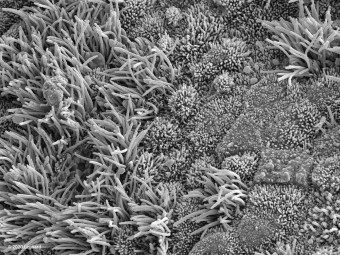

COVID-19 Infected Nasal Epithelial Tissue